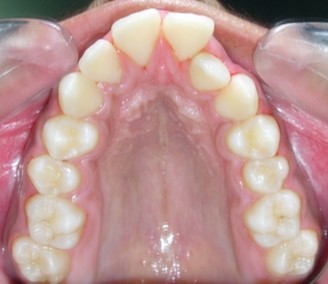

Intraoral assessment. (Figure 1d,Figure 1e,Figure 1f,Figure 1g,Figure 1h).

Figure 1g.Pre-treatment intra-oral-Upper occlusal

The maxillary arch was V-shaped with severely proclined and rotated maxillary incisors with a palatally placed 12. The mandibular arch was U-shaped with severe crowding of mandibular incisors, with 43 partially erupted and buccally placed with transpositioned 42 and 43, with 42 mesiolingually rotated, 33 distolingually rotated and 34 distolingually rotated and buccally placed.

Severe increase in overjet and deep bite were both observed. The maxillary midline coincided with the skeletal midline but the mandibular midline was shifted to the right side by 1 mm. Bilateral maxillary posterior crossbite was also observed. On right side the molar relation was Class I and on the left side it was Class II. The canine relation was Class II on the left side and the curve of Spee was increased.